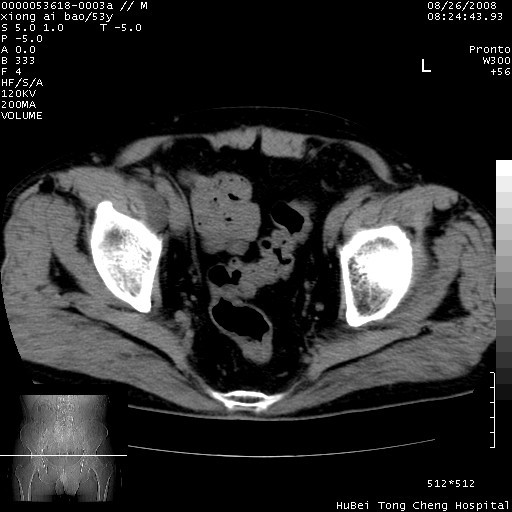

标题: CT15583:M,53Y。请老师指教分析骨盆及其他病变。 [打印本页]

标题: CT15583:M,53Y。请老师指教分析骨盆及其他病变。

股骨头坏死/腹股沟疝。

双侧股骨头无菌坏死,左侧腹股沟斜疝。

非常典型病例,双侧股骨头坏死伴双髋关节周围软组织肿胀,左腹股沟疝。

双侧股骨头坏死伴双髋关节周围软组织肿胀,左腹股沟疝。

双侧骨股头无菌性坏死,左侧腹股沟疝

双侧髋关节肿胀明显,感觉还不能排除结核。

考虑双侧髋关节结核,左侧腹股沟疝